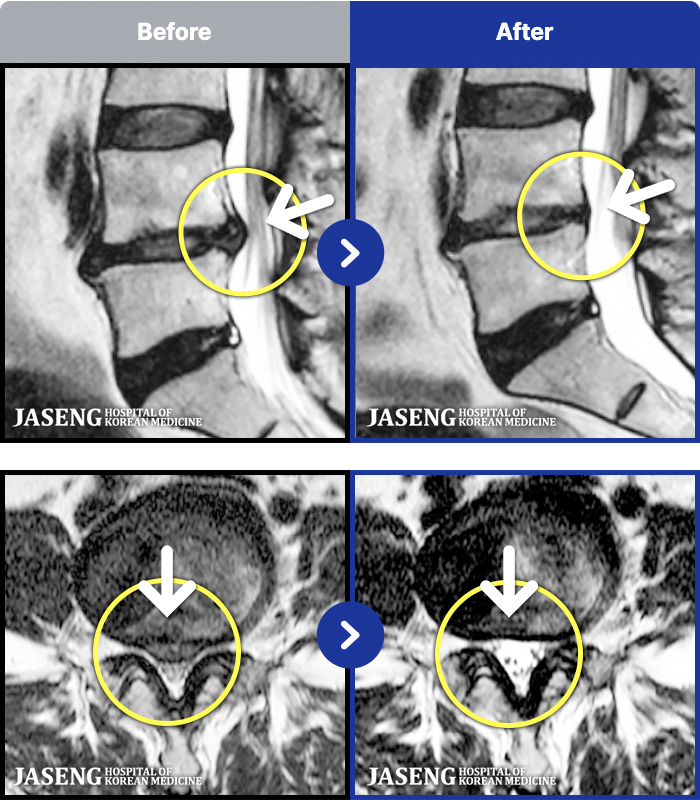

MRI ġ

1,299 MRI ũ ʸ Ȯϼ.